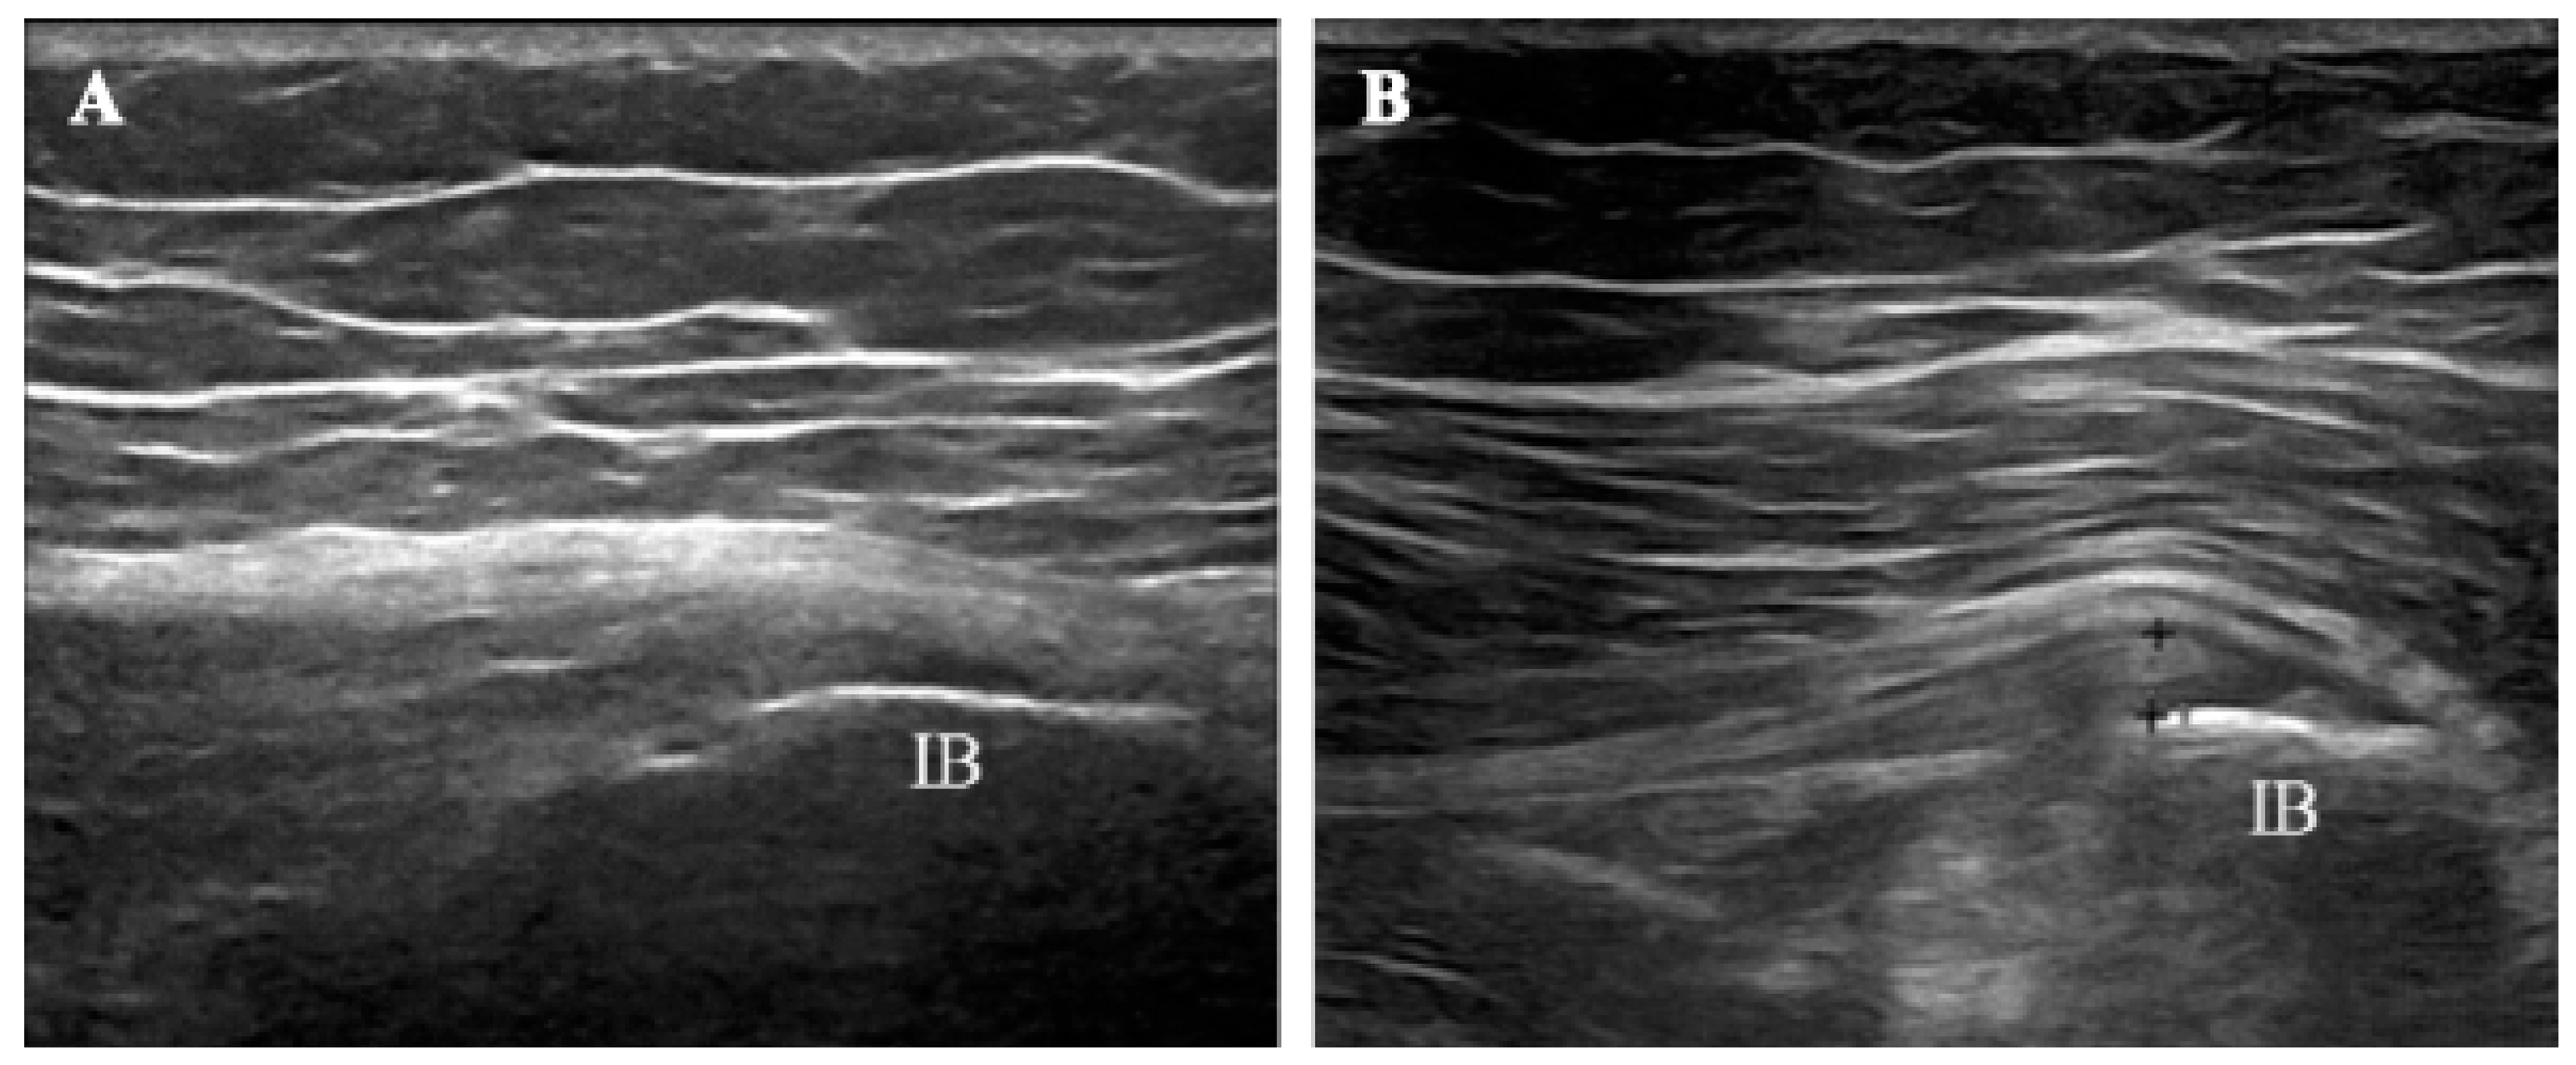

Treatment success rates were 90.9% and 81.8% at short- (T1) and long-term (T2) follow-up, respectively. Ultrasonography revealed a trend of reduction in hypoechoic thickening and an increase in fibrillar echotexture in gluteus medius tendons after combined ESWT (Figure 5). Furthermore, no serious adverse events were recorded, and combined ESWT was well tolerated by all patients.

Figure 5.

Longitudinal views of the gluteus medius tendon from a patient in the study before (A) and after (B) combined ESWT. At baseline, the ultrasound image showed hypoechoic thickening at the tendon’s insertion onto the iliac bone (IB). Irregularities of the tendon’s superior contour were also evident. In contrast, a marked improvement in the morphological aspect of the tendon was evident at T2, as shown by the more homogeneous tendon fibrillar pattern and reduced thickness.